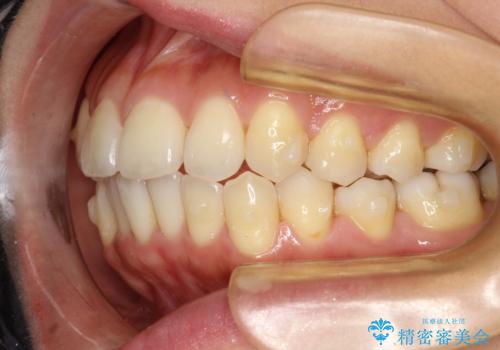

前歯が前後反対にかんでいる インビザラインによる目立たない矯正

- 前歯のかみ合わせを主訴に来院されました。

なるべく目立たずに矯正をしたいとのことで、インビザラインで矯正をすることとしました。

歯と歯の間をわずかに削り、ガタガタを改善しました。

目立たずに矯正を終えることができて、喜んでいただけました。